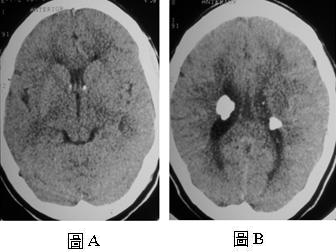

【110-2 醫學(四) 第74題】

32 歲女性患者有癲癇、心智遲緩的病史, ,接受電腦斷層檢查,2 張圖分別是未注射顯影劑的不同切面影像,下張圖分別是未注射顯影劑的不同切面影像列何者是最可能的診斷?